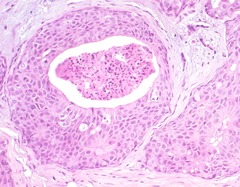

Comedo type

Front

-subtype of DCIS -shows necrosis -high grade 3 -solid or comedo growth patterns -high grade ductal carcinoma in situ, if there is a corresponding variation in nuclei or evidence of necrosis.